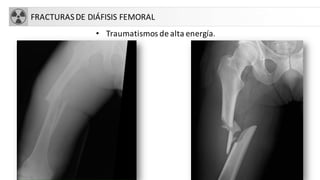

FRACTURASDE DIÁFISIS FEMORAL

• Traumatismos de alta energía.

FRACTURASDE DIÁFISIS FEMORAL •Traumatismos de alta energía.